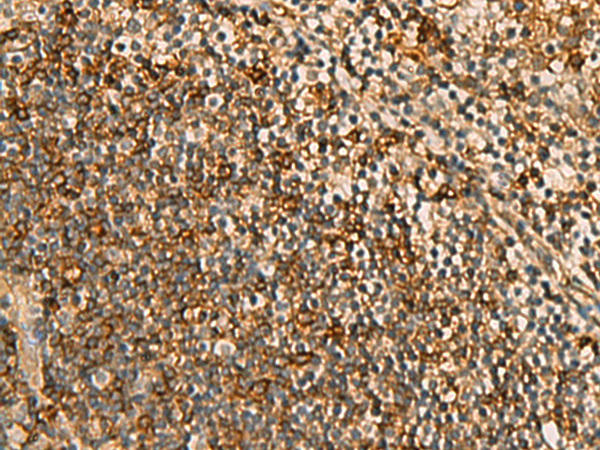

分类: 科研抗体货号: P10357别名: GNT-IV; GNT-IVB应用: IHC反应种属: Human, Mouse